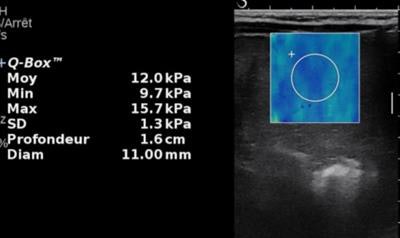

Same patient. Above: Elasticity of the mass is moderately increased (12 kPa). Second image: Elasticity of the liver parenchyma away from the mass is markedly increased (22.5 kPa). Last image: There is also a marked increase of spleen elasticity. In conclusion, the association of stiff liver and spleen is highly suggestive of chronic liver disease with a large regenerative nodule. This was confirmed by biology, which revealed tyrosinemia.Because radiologists are too focused on the lesion, they might sometimes overlook this vascular malformation, potentially the cause of the tumor, and often its solution.